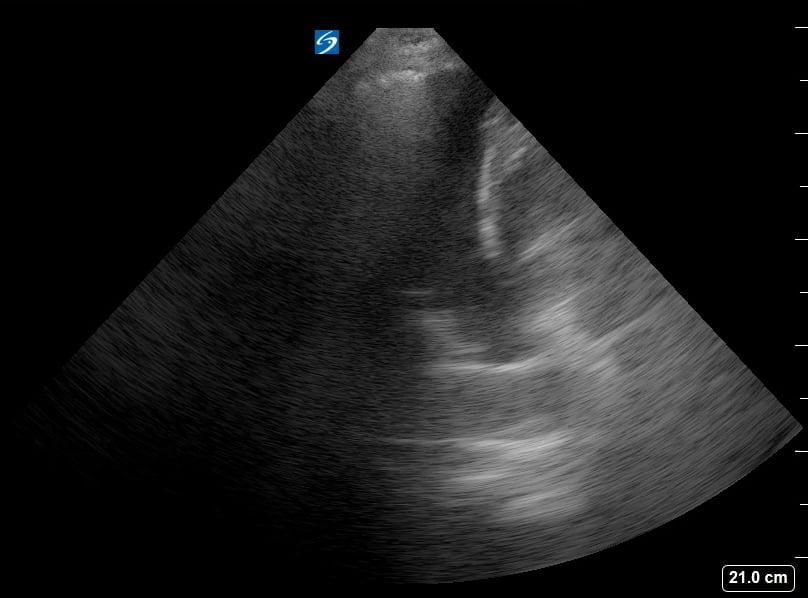

Pleural effusion in pediatrics refers to the abnormal accumulation of fluid in the pleural space, the area between the lungs and chest wall. In pediatric ultrasound, this condition is critical to diagnose, as it can indicate underlying issues like pneumonia, heart failure, or malignancy. Early and accurate detection through ultrasound is crucial for guiding treatment and improving outcomes in children.

Pediatric ultrasound is a highly effective, non-invasive tool for visualizing pleural effusions, offering real-time imaging without radiation exposure. Sonographers can assess the size, character, and location of the fluid, aiding in differentiation from other lung pathologies. Understanding the sonographic appearance of pediatric pleural effusions is essential for medical professionals for precise diagnosis and management.